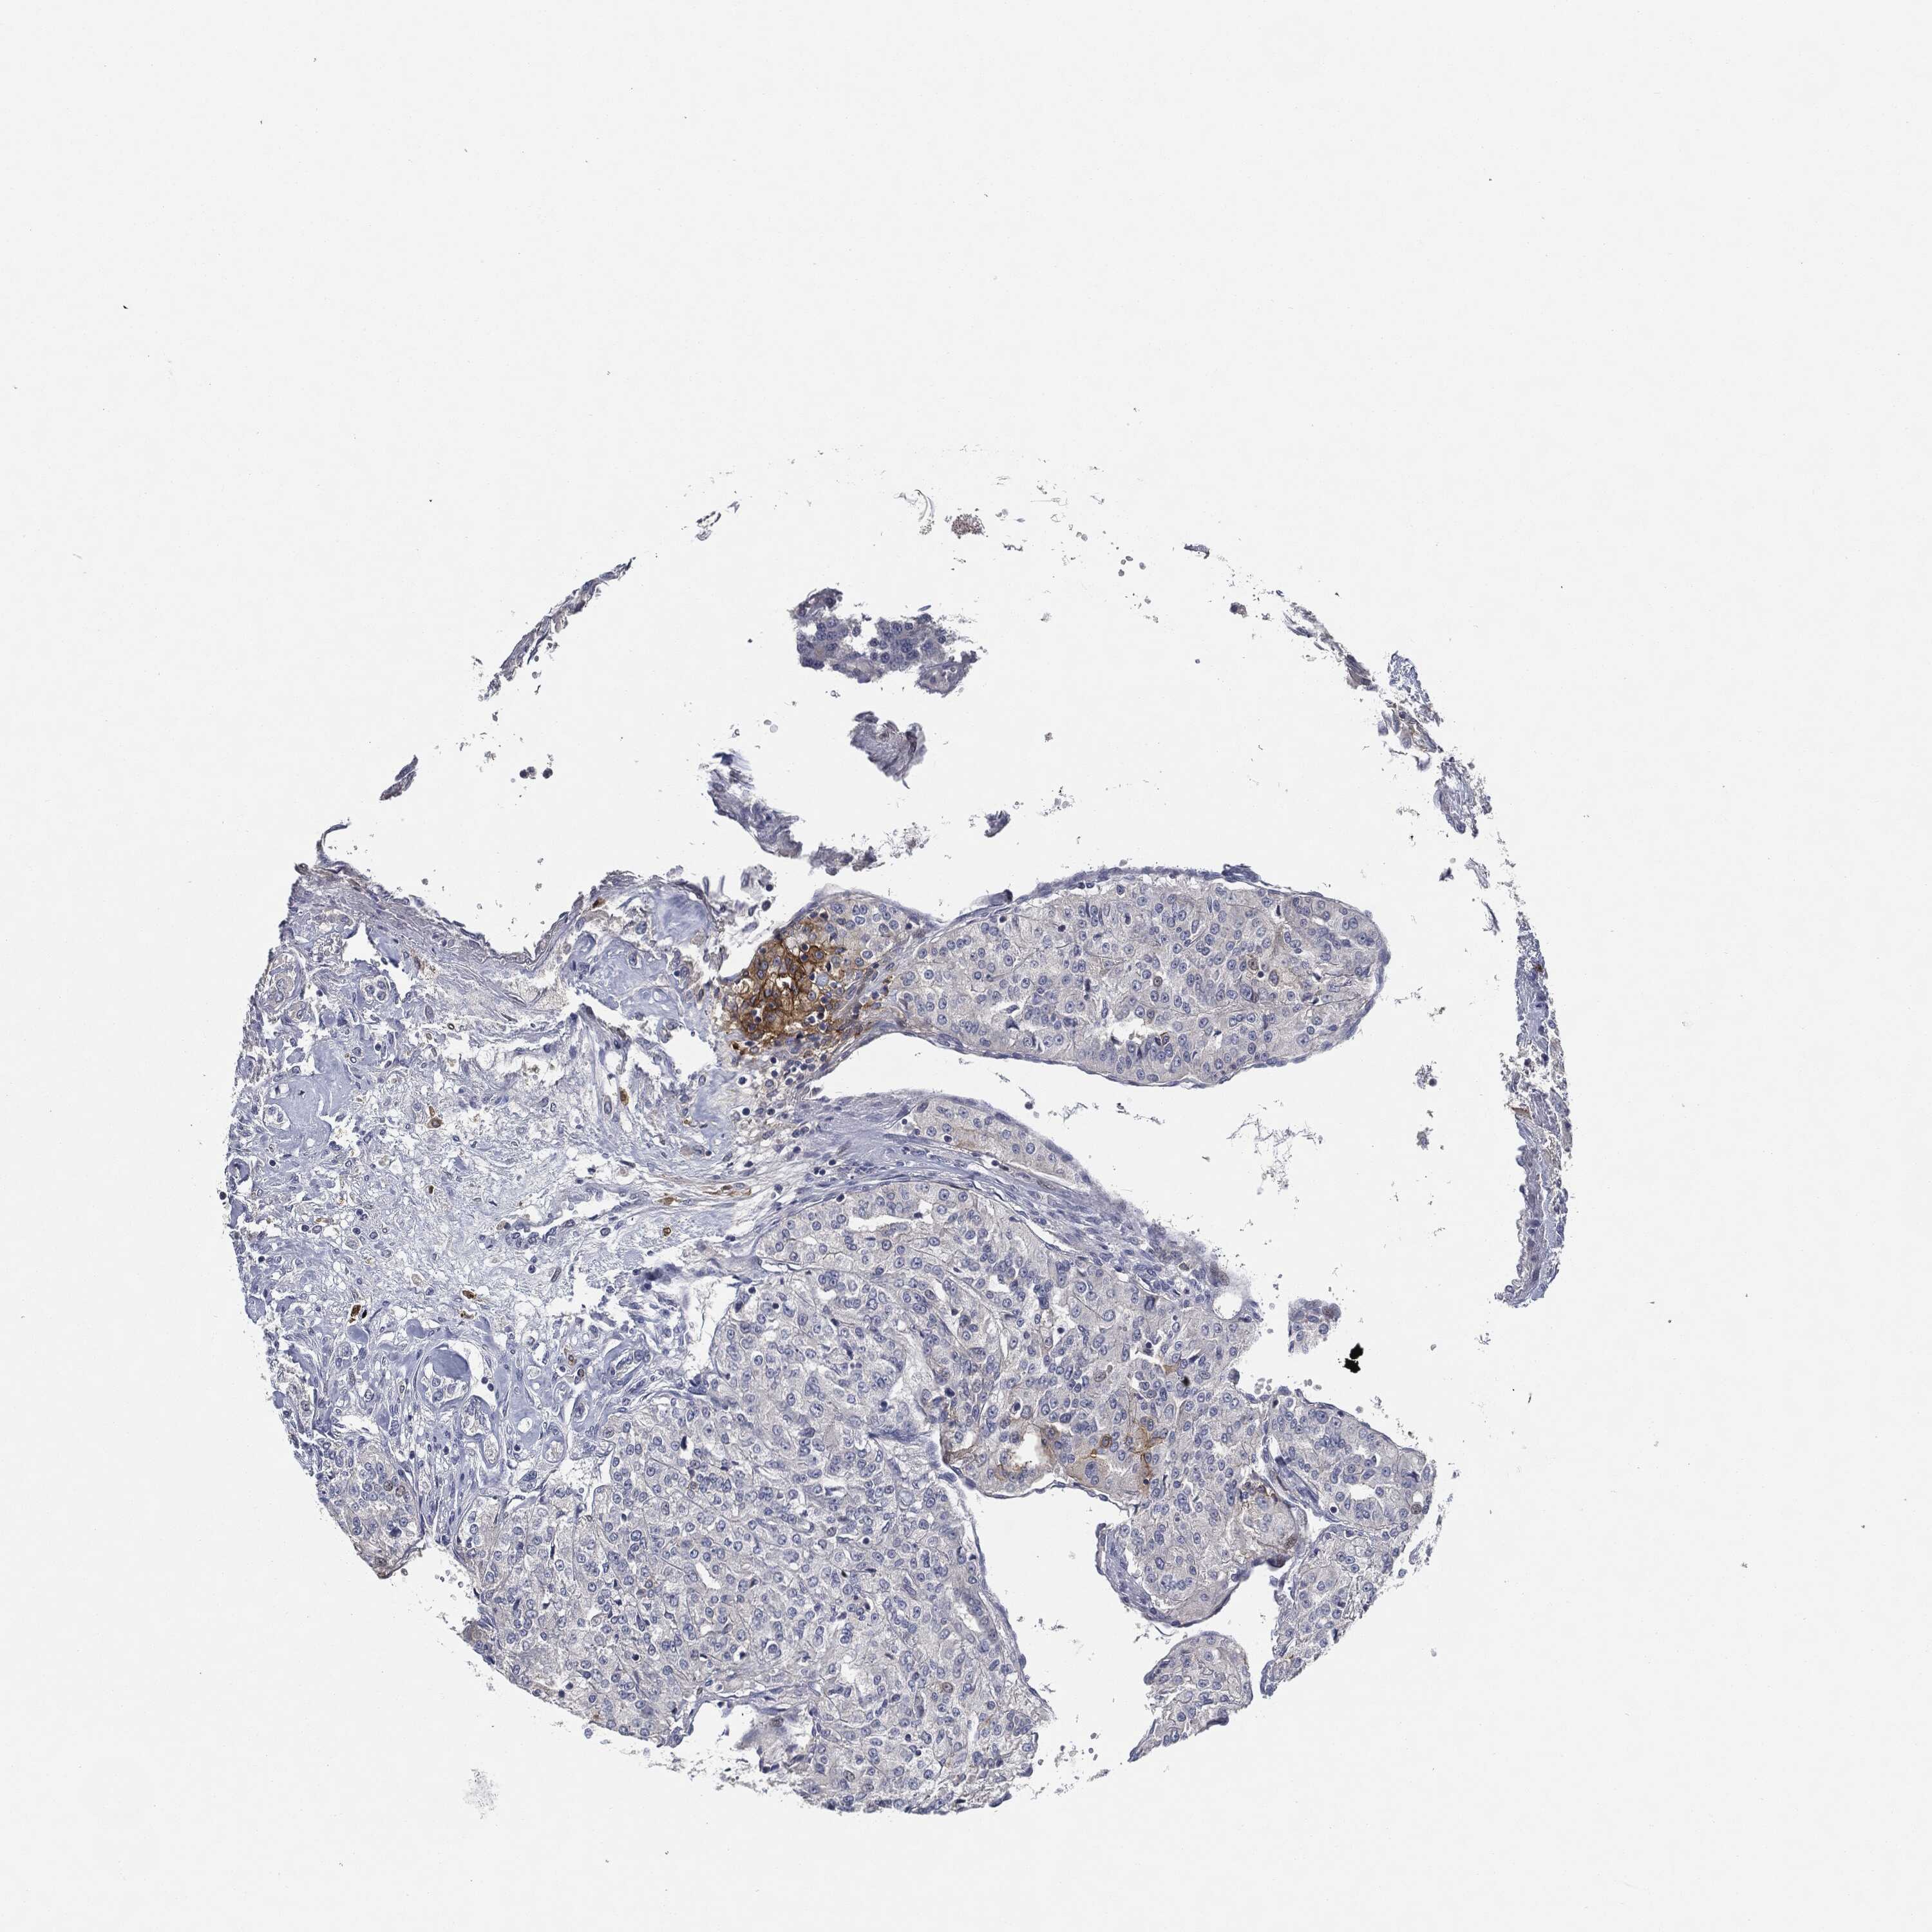

KIDNEY RENAL PAPILLARY CELL CARCINOMA (TCGA) - Interactive survival scatter ploti

The Survival Scatter plot shows the clinical status (i.e. dead or alive) for all individuals in the patient cohort, based on the same data that underlies the corresponding Kaplan-Meier plots. Patients that are alive at last time for follow-up are shown in blue and patients who have died during the study are shown in red.

The x-axis shows the expression levels (FPKM) of the investigated gene in the tumor tissue at the time of diagnosis. The y-axis shows the follow-up time after diagnosis (years). Both axes are complimented with kernel density curves demonstrating the data density over the axes. The top density plot shows the expression levels (FPKM) distribution among dead (red) and alive patients (blue). The right density plot shows the data density of the survived years of dead patients with high and low expression levels respectively, stratified using the cutoff indicated by the vertical dashed line through the Survival Scatter plot. This cutoff is automatically defined based on the FPKM cutoff that minimizes the p-score. The cutoff can be changed by dragging the vertical line or by entering a cutoff value in the square labeled "Current cut-off".

Under the Survival Scatter plot the p-score landscape (black curve; left axis) is shown together with dead median separation (red curve; right axis). Dead median separation is the difference in median mRNA expression between patients who have died with high and low expression, respectively. It is calculated as follows: median FPKM expression of dead patients with high expression - median FPKM expression of dead patients with low expression. This is intended to aid the user in visually exploring custom cutoffs and the associated p-scores and dead median separation.

Individual patient data is displayed and can be filtered by clicking on one or more of the category buttons on the top of the page. Categories describing expression level and patient information include: high, low, alive, dead, female, male and tumor stages. The scale of the x-axis can be toggled between linear and log-scale by clicking on the "x log" button. Mouse-over function shows TCGA ID, patient information and mRNA expression (FPKM) for each patient.

& Survival analysisi

Kaplan-Meier plots summarize results from analysis of correlation between mRNA expression level and patient survival. Patients were divided based on level of expression into one of the two groups "low" (under cut off) or "high" (over cut off). X-axis shows time for survival (years) and y-axis shows the probability of survival, where 1.0 corresponds to 100 percent.

CD274 is not prognostic in Kidney Renal Papillary Cell Carcinoma (TCGA)

: 0.9